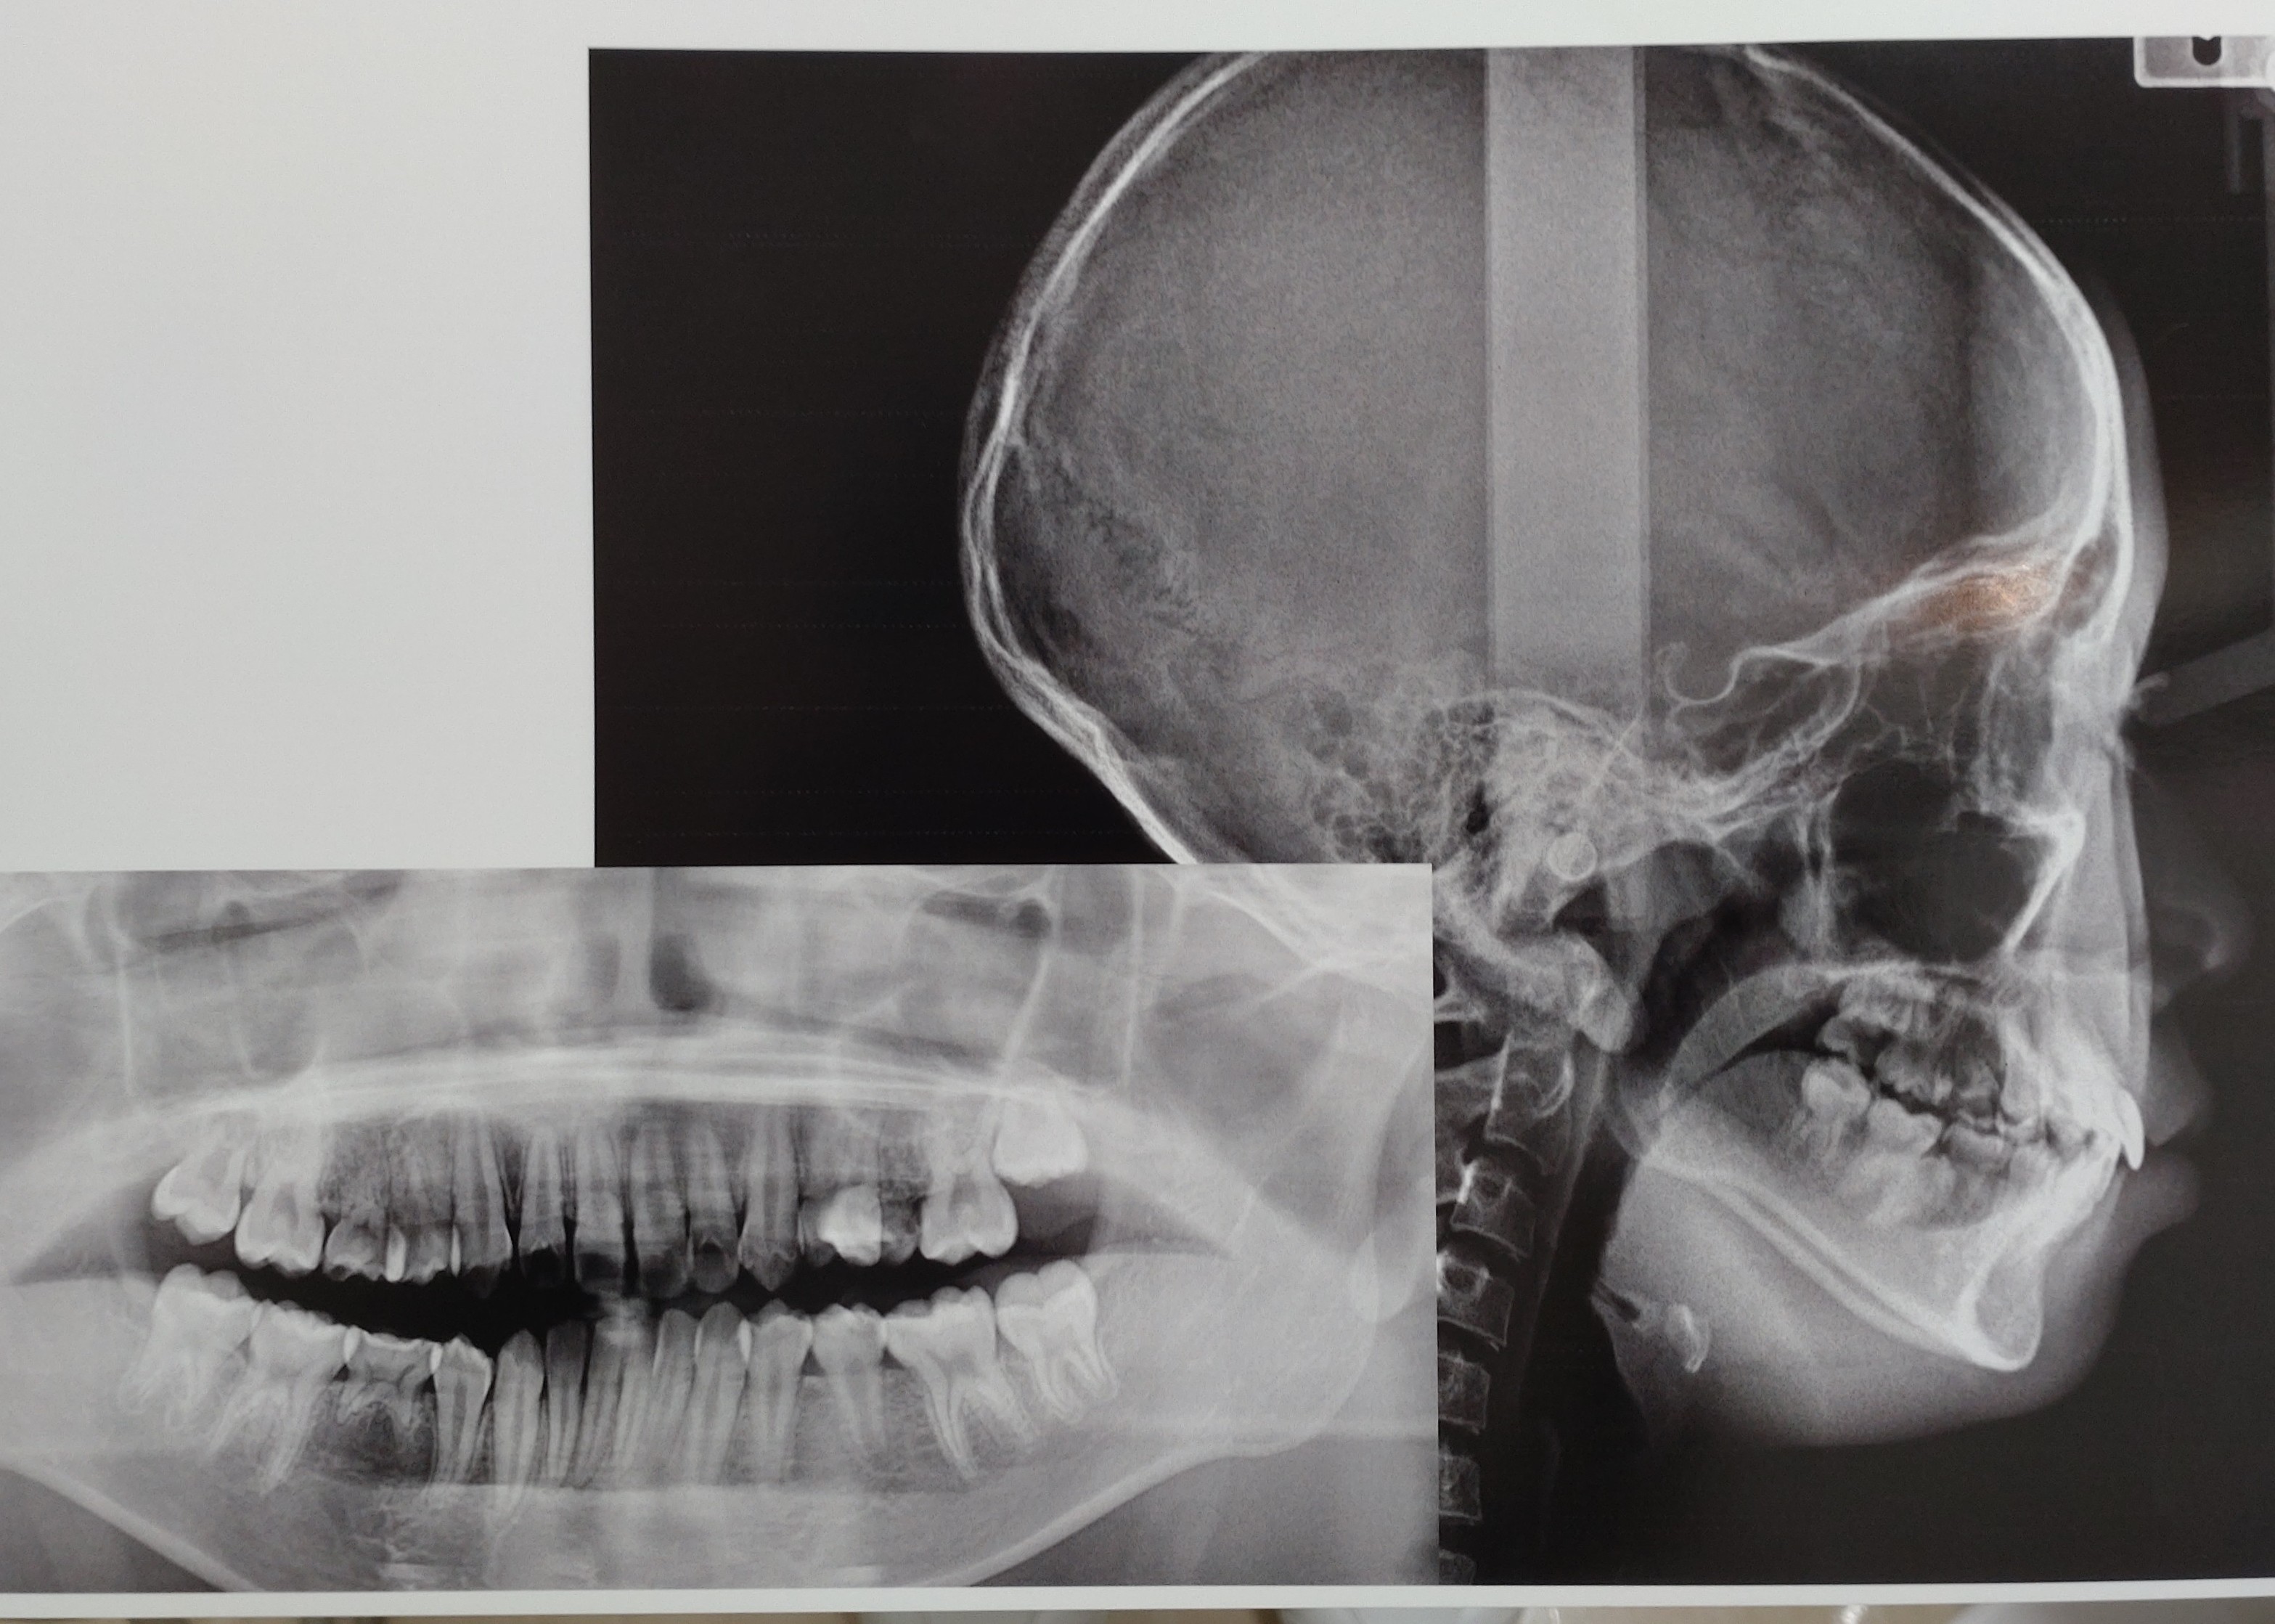

13歳の娘は後続のないEを3本抜歯して矯正する計画で、6番にバンド装着し間もなくEと唯一生え変わった5番1本を抜歯します。

上顎左右5番、下顎右側5番先天性欠損

以前、幅の大きなE3本抜歯しての矯正は前歯が引っ込みすぎないかと質問しましたが、逆に、1,2,3,4番対6,7番で引き合えば奥歯が前方に移動してしまい前歯は思うほど下がらないのでしょうか?

まだ左上7が生えていません。レントゲンを見ると左側7番が手前6番に引っ掛かっているように見えので衛生士さんに言うと「矯正始めると6番も動いて解放されるので大丈夫ですよ」と言われました。それまでのんびり待っていても大丈夫なのでしょうか?

画像1

画像2

セファロを見て、前歯は3ミリほど下がる。

上顎のEを抜いた大きなスペースは半分は前歯を後方に、奥歯を前方に移動させる。下顎は噛み合わせを考慮してすすめる。

左上7番は引っかかってはいないだろう。